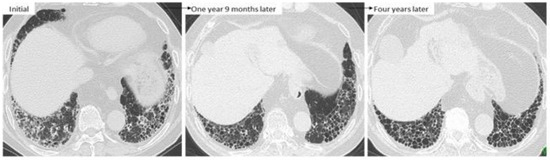

4.2. Disease Behavior

4.3. Predictors of ILD Progression and Prognostic Factors